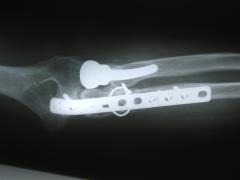

Περίπτωση 2ου ασθενούς

1 χρόνo μετά το χειρουργείο